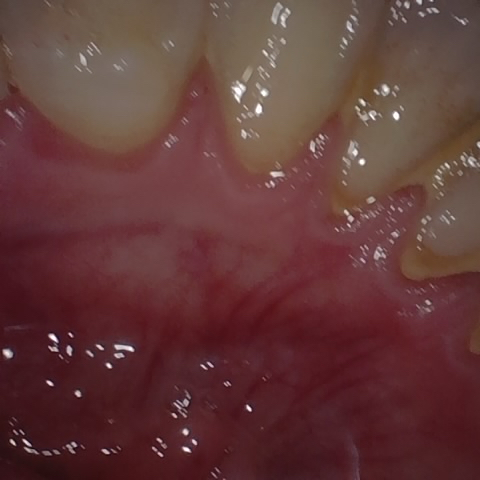

Annotated as "Good"